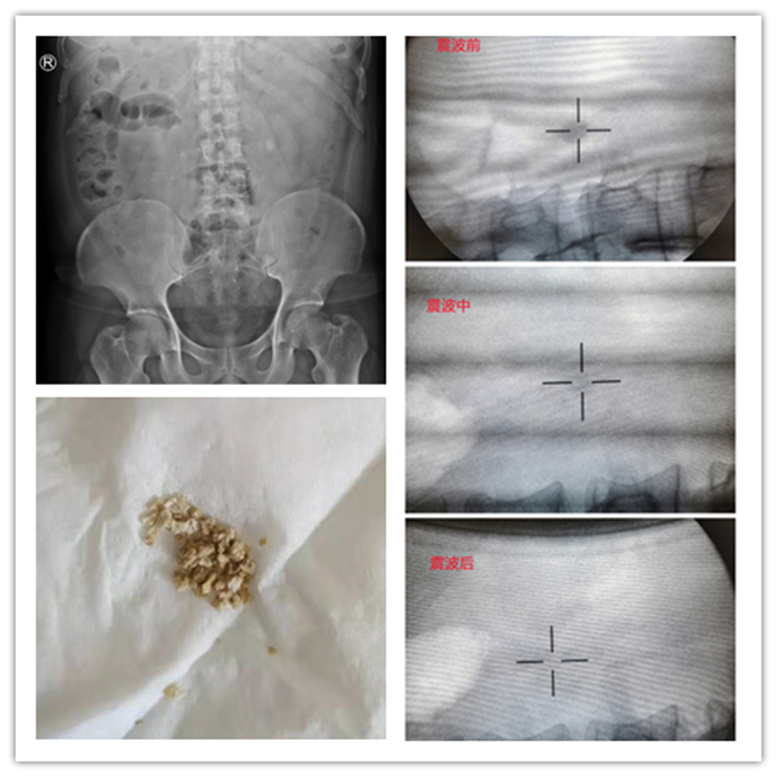

典型病例:

患者刘某,左侧肾绞痛1h入院,查B超、KUB示:左侧输尿管上段结石1.5cm,予以体外冲击波碎石,体外冲击3018次,总能量83.77J,治疗时间50min,术后3天复查B超示结石已排尽。